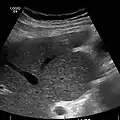

Ultrasound is routinely used in the evaluation of cirrhosis. It may show a small and nodular liver in advanced cirrhosis along with increased echogenicity with irregular appearing areas. Other liver findings suggestive of cirrhosis in imaging are an enlarged caudate lobe, widening of the fissures and enlargement of the spleen. An enlarged spleen (splenomegaly), which normally measures less than 11–12 cm in adults, can be seen and may suggest underlying portal hypertension. Ultrasound may also screen for hepatocellular carcinoma, portal hypertension, and Budd-Chiari syndrome (by assessing flow in the hepatic vein). An increased portal vein pulsatility is an indicator of cirrhosis, but may also be caused by an increased right atrial pressure.[33] Portal vein pulsatility can be quantified by pulsatility indices (PI), where an index above a certain cutoff indicates pathology: